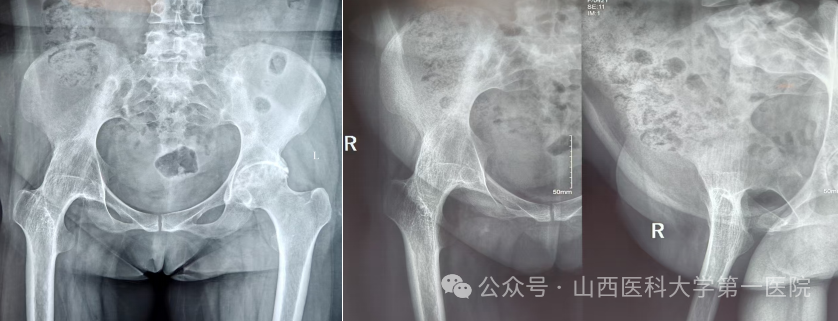

一名42岁的强直性脊柱炎患者,多年来饱受病痛折磨。随着病情进展,双侧髋关节逐渐“锈死”,无法弯腰、下蹲,甚至连坐下都成了奢望——吃饭只能站着,休息只能躺着,生活自理能力几乎丧失。接诊后,骨科杨自权主任团队对患者进行全面检查,发现患者不仅脊柱强直呈“板状腰”,双侧髋关节出现严重融合,而且双膝、双踝关节功能明显下降,手术难度极大。

强直性脊柱炎伴髋关节病变的置换手术,被誉为骨科领域的“硬仗”。杨自权总结此类患者三大诊疗难点:一是麻醉困难,患者脊柱强直,常无法配合常规麻醉体位;二是解剖变异,长期炎症导致关节周围骨质疏松、肌肉萎缩,手术视野不清,风险极高;三是对手术精度要求更高,假体安放的位置、角度稍有偏差,就会影响术后关节稳定性及使用寿命。